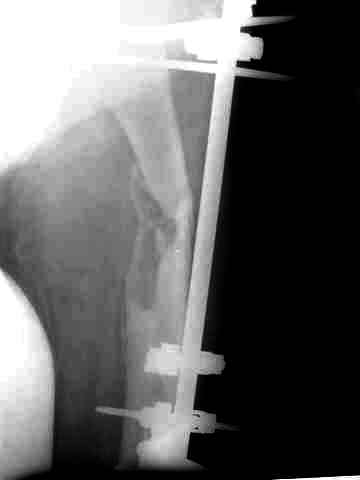

Через 3 года после травмы констатировало отсутствие консолидации бедренной кости, сохранение признаков хронического остеомиелита (свищ в нижней трети левого бедра). Произведен демонтаж аппарата, реостеосинтез бедренной кости спице-стержневым аппаратом, некрсеквестрэктомия. В аппарате удалось лишь частично произвестиустранение углообразной деформации бедренной кости [image 05] .